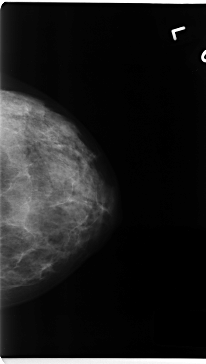

C_0167_1.LEFT_CC

LEFT_CC LINES 4728 PIXELS_PER_LINE 2672 BITS_PER_PIXEL 12 RESOLUTION 50 NON_OVERLAY